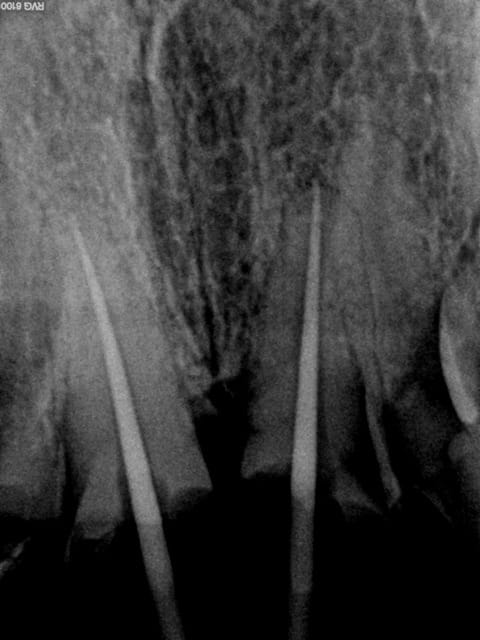

Endos sans digue, avec de la carie résiduelle, la gutta/ciment ne remplit pas toute la lumière du canal, pas de respect de l'espace biologique, effet férule minimaliste.....

Vu les autres dents le patient ne mérite peut être pas mieux et l'indication est là mieux posée, mais tu te positionnes comme un pro de l'endo puisque tu en ferais souvent et là, c'est pas flagrant...

Par contre top rentabilité !